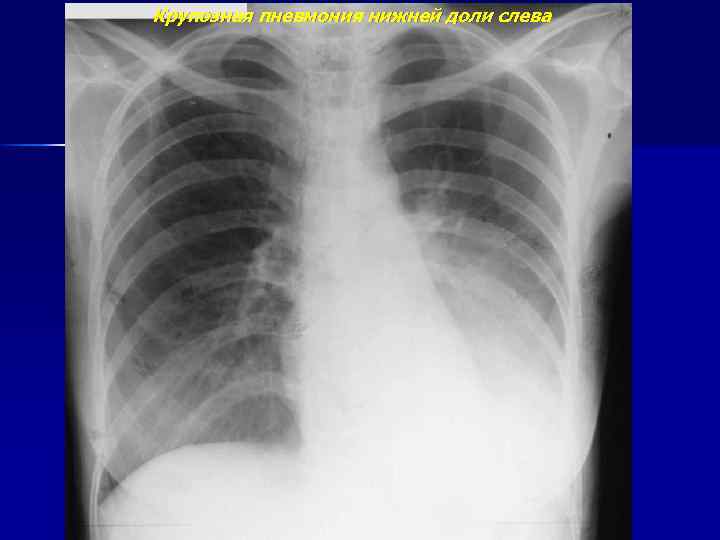

Крупозная пневмония нижней доли слева